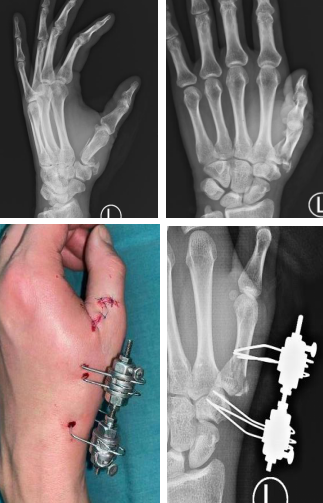

Ilizarov技术应用几乎涵盖了所有骨科领域,甚至一些交叉学科。如骨与软组织缺损、骨不连、畸形矫正、骨关节病、器械构型改进、糖尿病足等。我院手外科朱辉主任接触Ilizarov外固定支架后早期的一些临床应用病例,解决了在淮海经济区被认为时非常棘手的问题,包括手部掌指骨的开放或闭合骨折;手指、手腕的再植;骨不连、畸形愈合、假关节、截止残端、发育不良;先天短缩畸形,先天并指畸形及关节挛缩等。使用Ilizarov显微手足外固定器(IMEF)治疗掌、指骨骨折,Ilizarov显微手足外固定器的优点突出,固定牢固,操作方便,可以避开血管神经肌腱、不影响关节活动,构型更加个性化、多样化。

掌骨骨折,闭合复位,微创操作。